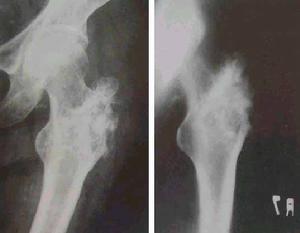

骶髂關節結核--影像檢查時在站立位脊柱前彎、後伸及側彎均受限,並有局部疼痛,但坐位時活動較好。臥位直腿抬高試驗,患側受限並有局部疼痛。壓擠或分離髂骨時患部疼痛,骶髂關節患部有壓痛,可有寒性膿腫或竇道。肛指檢查有時可摸到局部膿腫及壓痛。X線照片檢查對早期診斷很重要,需照骶髂關節正位及斜位(關節的矢狀面),可見骨質破壞、死骨及空洞形成等。

骶髂關節結核--CT主要根據其臨床表現和輔助檢查的結果,主要是X線檢查。檢查時在站立位脊柱前彎、後伸及側彎均受限,並有局部疼痛,但坐位時活動較好。臥位直腿抬高試驗,患側受限並有局部疼痛。壓擠或分離髂骨時患部疼痛,骶髂關節患部有壓痛,可有寒性膿腫或竇道。本病的輔助檢查方法主要依靠X線和CT檢查,其表現主要有以下幾個方面:

1、病變部位:骨型關節結核主要在骶髂關節前下1/3髂骨松質部。滑膜結核也可穿破關節軟骨而侵入骨組織,引起骶髂關節面及骨組織破壞。

2、骨質破壞:骨型關節結核骨破壞區呈圓形或橢圓形,破壞區邊緣可見,骶髂關節間隙無明顯狹窄。滑膜型關節結核表現為骶髂關節面不同程度的模糊或糜爛,其間隙不同程度的狹窄或增寬;有的顯示骨質明顯破壞,關節間隙不規則增寬。

骶髂關節結核--病變部位4、骨質增生硬化:骶髂關節結核無瘺管形成,未發生繼發感染亦可出現骨質增生硬化,其原因在於骶髂關節結核的骨質疏鬆常不如其他關節明顯,而往往顯示有骨質增生硬化徵象。

X線攝片早期關節面模糊,邊緣糜爛,關節間隙增寬,晚期關節間隙變窄。並有竇道,常繼發感染。關節呈現硬化。關節破壞嚴重者同側髂骨和恥骨可上移發生病理脫位。